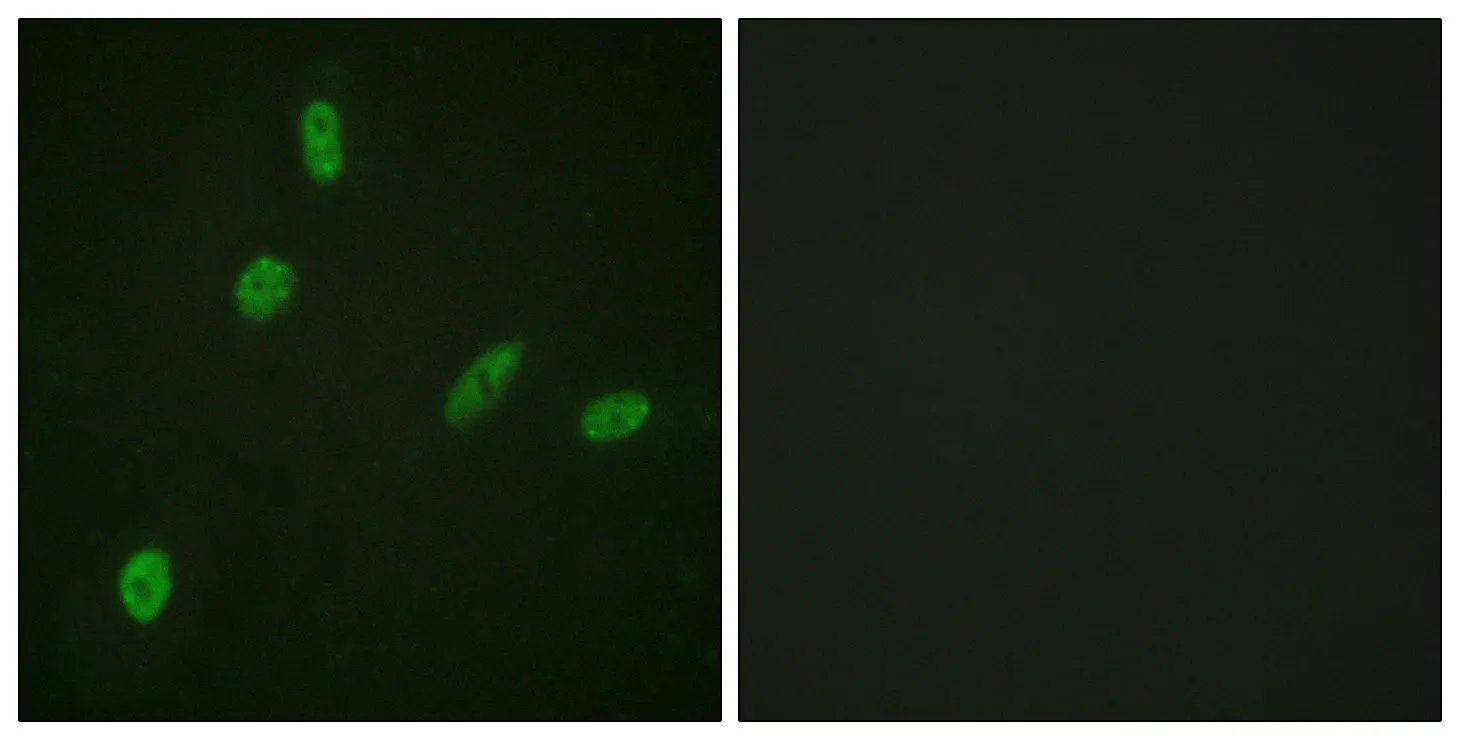

ETS1 Rabbit Polyclonal Antibody

Cat: APRab10649